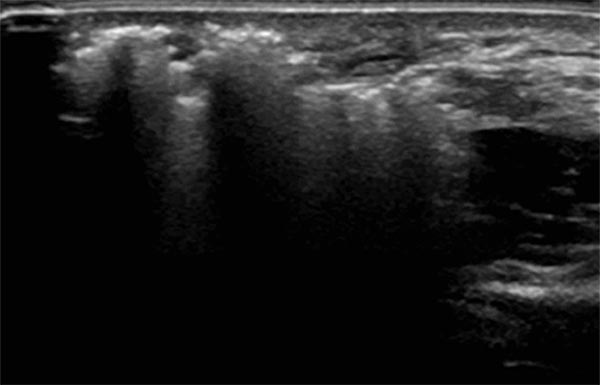

Sonography during sclerotherapy treatment. At the right side of the picture the still unfilled parts of the venous malformation, shown black as nearly echo-free vascular channels. On the left side lesion already filled by the sclerosing foam, echogenic with dorsal acoustic shadowing.